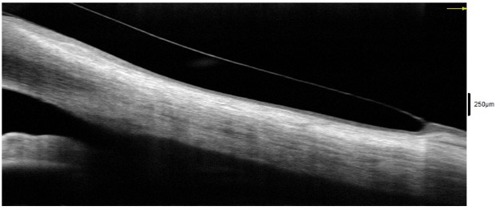

The excessive inferior clearance was not concerning, as there were no signs of conjunctival swelling or prolapse on OCT (see Figure 3) and no limbal hyperemia on slit lamp examination. Good edge alignment was found at 360º, showing conjunctiva covering half of the lens edge thickness on OCT. The trial was dispensed to the patient, and a follow-up exam was completed 1 week later. At the follow-up appointment, after 5 hours of lens wear, the central clearance was 205 µm, the limbal zone showed no change, and no conjunctival prolapse was found inferiorly in the area of excessive limbal clearance. The edge alignment was improved superiorly and temporally, no blanching was present on slit lamp evaluation, and the patient reported no foreign body sensation. The lens was removed, and sodium fluorescein stain was instilled. No staining or impression ring pooling were present on the cornea or conjunctiva. The scleral lens prescription was finalized, and the patient was instructed to return to care in 6 months for a scleral lens progress examination and possible fitting of the right eye.

The ideal fit of a scleral lens shows a central clearance of around 200 µm, no limbal touch, and edge alignment with the sclera. On OCT, the limbus can be seen as a reflectivity change in the cornea (see Figure 4). This area should not be touched by the lens but should also not have excessive clearance, as negative pressure forces can pull the conjunctiva into that zone and cause conjunctival prolapse (see Figure 5) or excessive limbal hyperemia. OCT can also assist with evaluation of edge alignment. Appropriate edge alignment will be shown when the conjunctiva overlies half or more of the edge thickness, as seen in Figure 6, but does not fold over the edge of the lens.